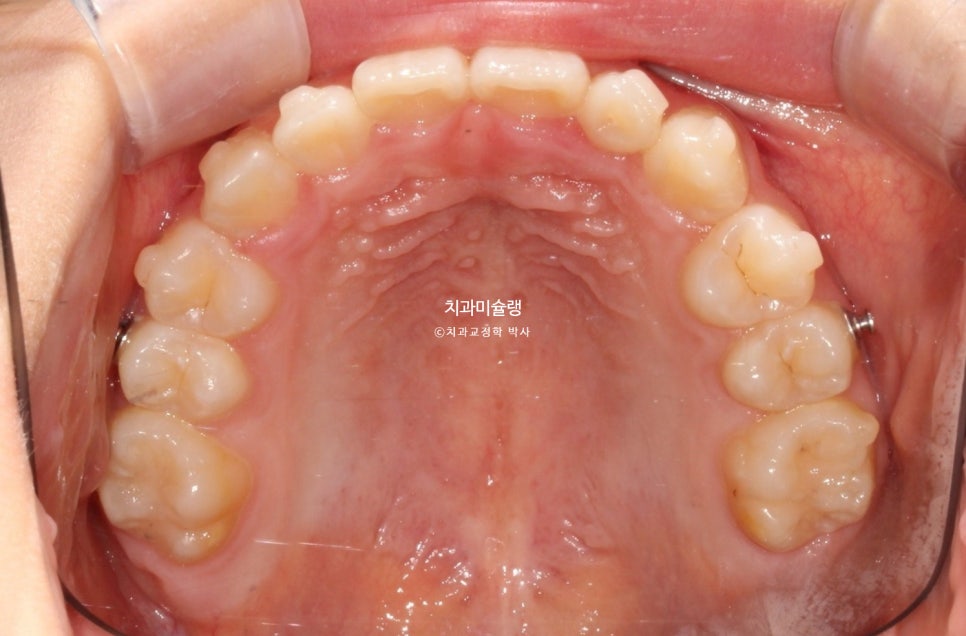

치료 완료 시 결과

중심선은 잘 맞으며 절단교합으로 인항 개방교합은 해소되었습니다.

어금니 교합관계는 1급을 달성.

3급 교합관계를 1급으로 만들기 위해 치료기간 내내 3급 고무줄을 사용했습니다.

결과가 성인교정치료 결과에 준한만큼 유지장치도 성인과 동일하게 들어갑니다.